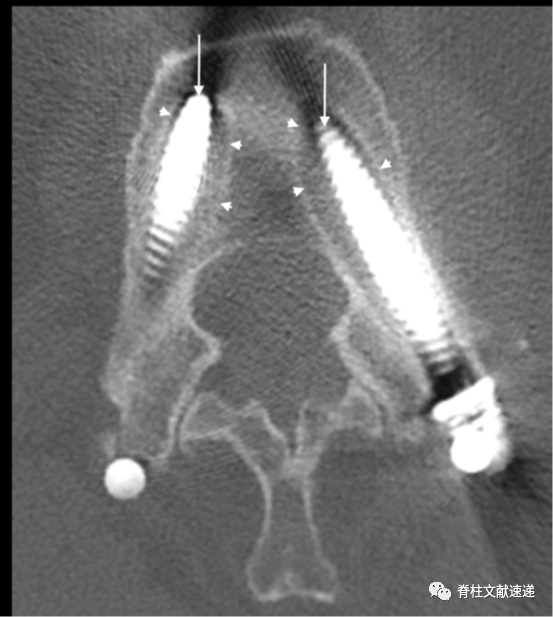

CT检查发现螺钉松动的征象

本文中CT显示的松动螺钉